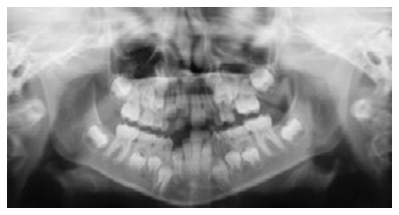

Dental Radiographs (X-Rays)

Radiographs (X-Rays) are a vital and necessary part of your child’s dental diagnostic process. Without them, certain dental conditions can and will be missed.

The American Academy of Pediatric Dentistry recommends radiographs and examinations every six months for children with a high risk of tooth decay. On average, most pediatric dentists request radiographs approximately once a year. Approximately every 3 years, it is a good idea to obtain a complete set of radiographs, either a panoramic and bitewings or periapicals and bitewings.

Radiographs detect much more than cavities. For example, radiographs may be needed to survey erupting teeth, diagnose bone diseases, evaluate the results of an injury, or plan orthodontic treatment. Radiographs allow dentists to diagnose and treat health conditions that cannot be detected during a clinical examination. If dental problems are found and treated early, dental care is more comfortable for your child and more affordable for you.

Pediatric dentists are particularly careful to minimize the exposure of their patients to radiation. With contemporary safeguards, the amount of radiation received in a dental X-ray examination is extremely small. The risk is negligible. In fact, the dental radiographs represent a far smaller risk than an undetected and untreated dental problem. Lead body aprons and shields will protect your child. Today’s equipment filters out unnecessary x-rays and restricts the x-ray beam to the area of interest. High-speed film and proper shielding assure that your child receives a minimal amount of radiation exposure.